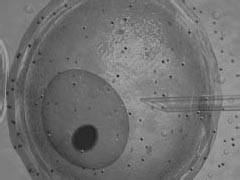

5、体外受精

6、胚胎培养

7、胚胎移植

9、胚胎观察